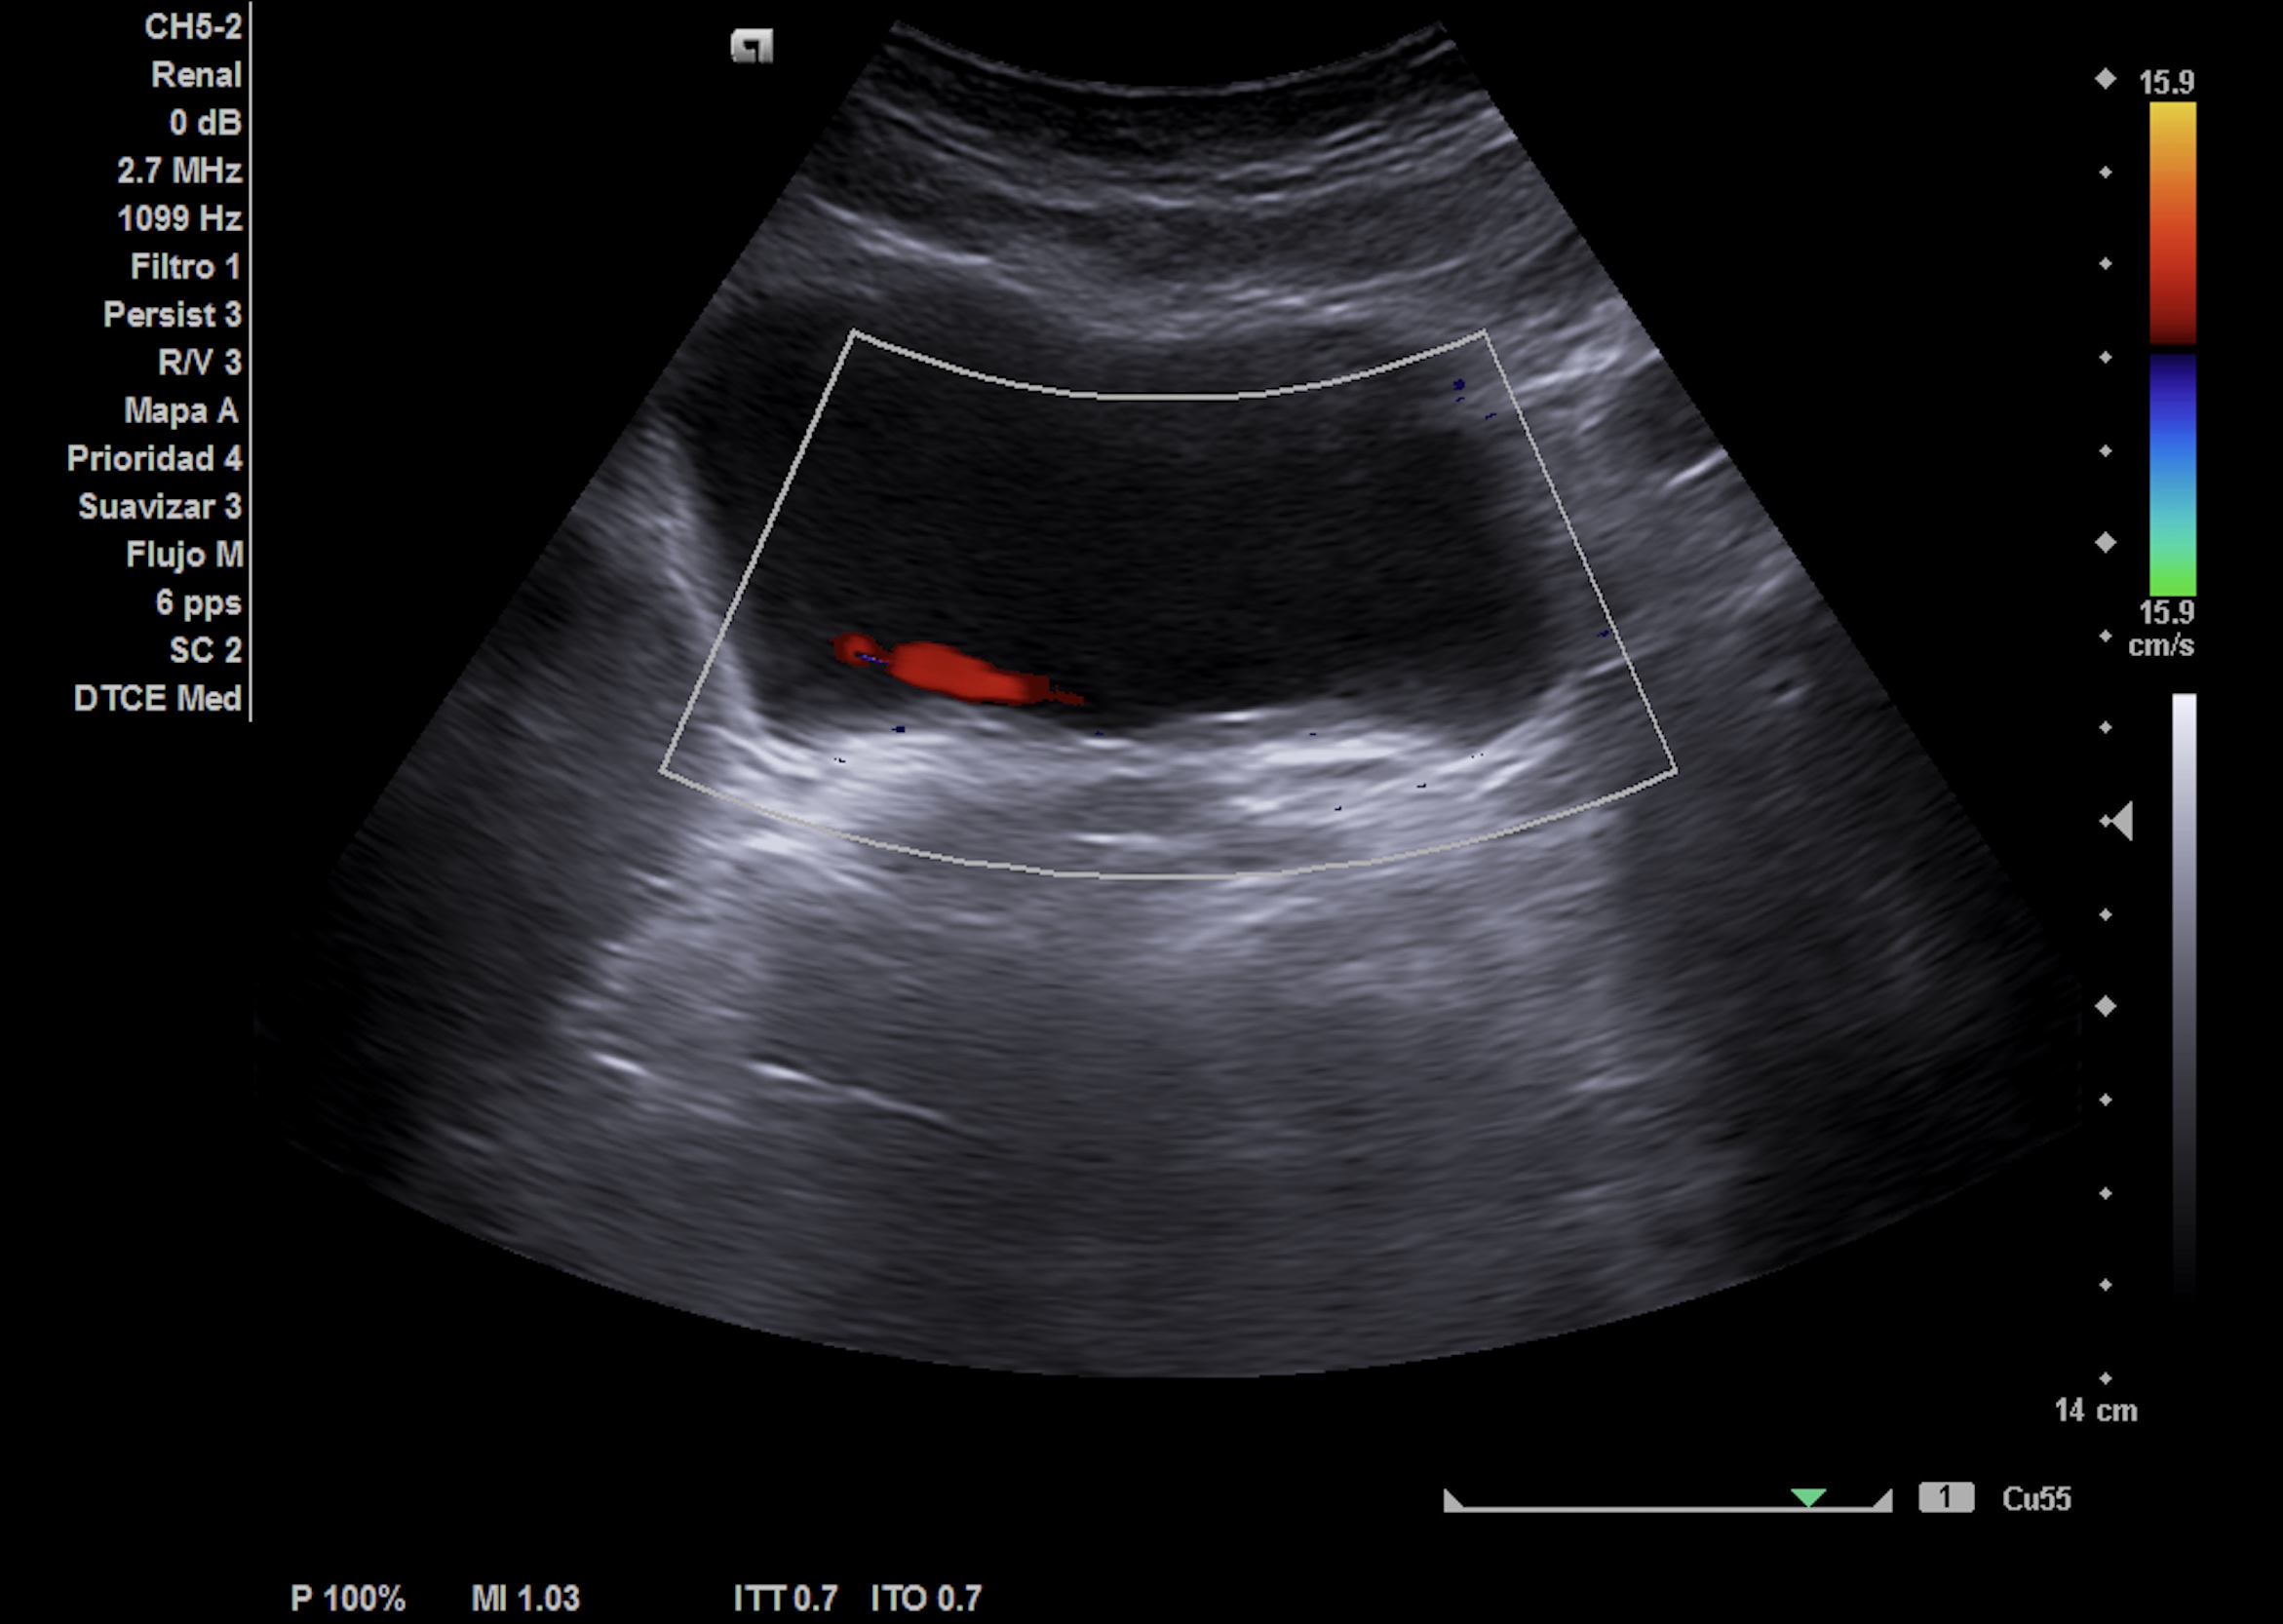

Nueva ecografía clínica renal, vías urinarias y vejiga (a la semana): hidronefrosis grado II que no presentaba hace 1 semana, no nefrolitiasis en cálices renales. Jet ureteral dcho permeable, en zona intermedia de uréter dcho presenta cálculo de 8 mm enclavado en el cruce de los vasos ilíacos con uréter.

Ecografía abdominopélvica urgencias hospital: Ureterohidronefrosis grado II derecha secundaria a litiasis de 7 mm en el uréter medio. Quiste cortical simple de 2.6 cm en el polo inferior.